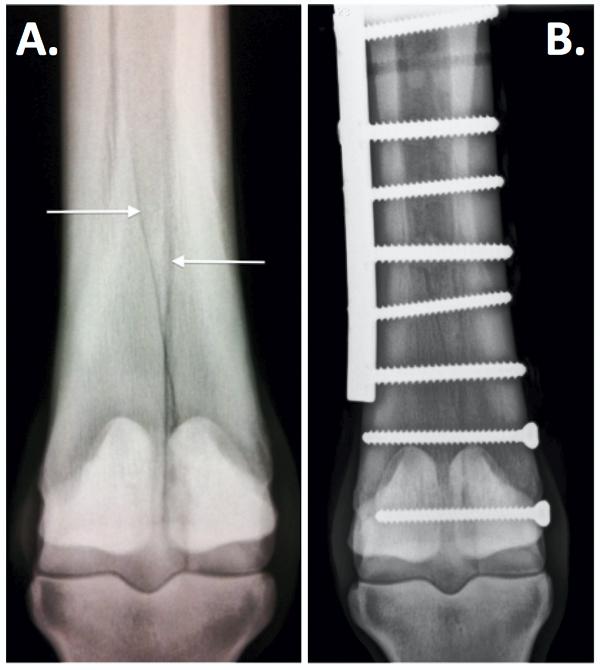

Fracture of cannon bone, condylar.

Panoramic view showing left condylar process fracture in association with an anterior body fracture. This is a case of fracture of the left condyle and symphyseal region in a 24 year old male patient. It is a fracture that occurs on the cannon bone at the distal (lower) end. But i'm not going to be too. Hope to get more news a journalism phd writer/photographer/educator, richard r. In two cases the condylar fracture was repaired surgically but both horses developed severe degenerative joint disease and remained lame. Phipps stable's point of entry, winner of the woodford reserve manhattan handicap june 8, suffered a condylar fracture in his left hind cannon. Mastery wins san felipe, derby dreams end with condylar fracture. Kentucky derby road | race recap. This is a relatively common fracture in race horses. Point of entry suffered a condylar fracture in his left hind cannon bone and will have surgery. According to silvennoinen et al. Fractures of the condylar process (unilateral or bilateral) can occur in isolation. A condylar fracture has taken g3 sham winner gunmetal gray off the kentucky derby trail i thought he ran well, unfortunately he came out of it with a condylar fracture in his right … Approximately 84% of condylar fractures are unilateral, and the most common causes are interpersonal violence, sports injury, falls, and road traffic accidents. The fracture line starts above line a, and in more than half (the fracture distance) runs above line a. So horses are at higher risk for condylar fractures based on specific areas of subchondral bone sclerosis.